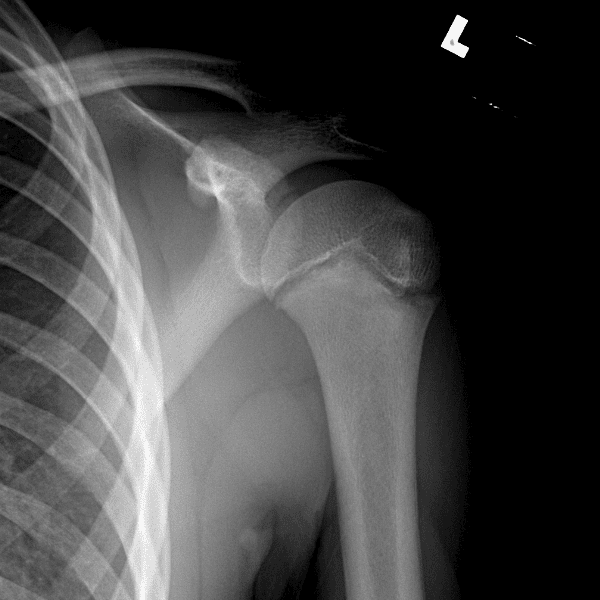

Simuliert den Dienst durch subtile oder schwierige Fälle und einige Normalbefunde.

30 Fälle